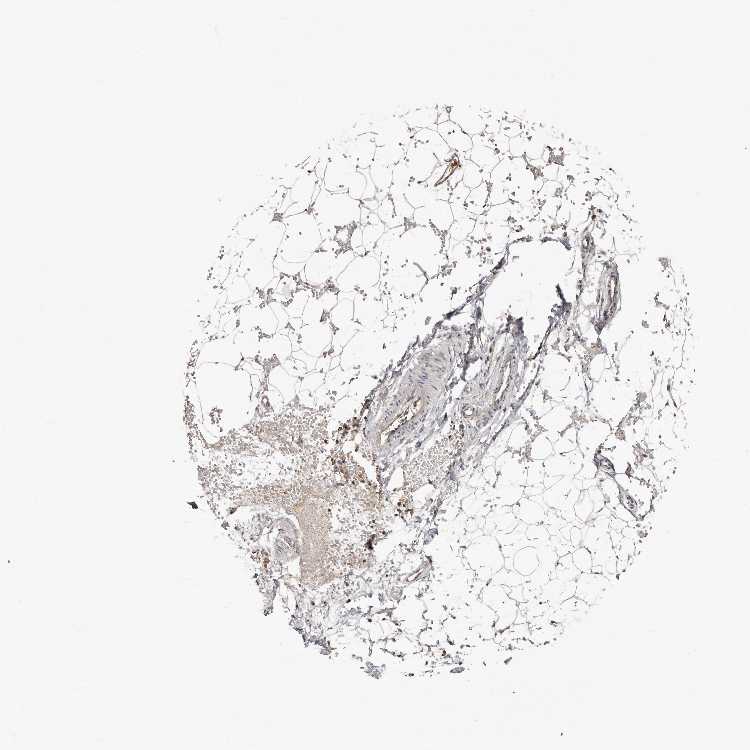

ADIPOSE TISSUE - Antibody stainingi

Antibody staining in the annotated cell types in the current human tissue is reported as not detected, low, medium, or high, based on conventional immunohistochemistry profiling in selected tissues. This score is based on the combination of the staining intensity and fraction of stained cells.

Each image is clickable and will lead to virtual microscopy that enables deeper exploration of all samples and also displays staining intensity scores, fraction scores and subcellular localization as well as patient and tissue information for each sample.

Antibody HPA029505Antibody HPA029506

Adipocytes LowNot detected